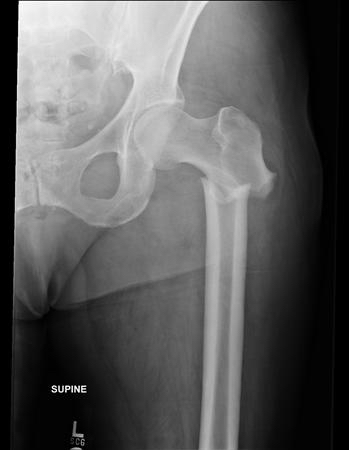

This paper is an example of how ACHA is co-operating with other research centres, in this case the Unit for Injury, Recovery and Inflammation Science at the University of Nottingham, and how our close links with the Centre for Bone and Joint Health at Queen Mary University of London can help develop important research in North East London. You can access the full paper here.